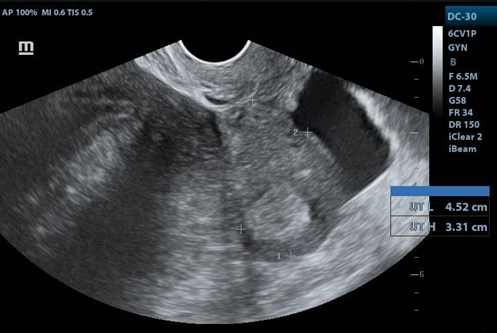

USG Transvaginal

1. Image of the uterus in longitudinal view. With free fluid in the cul de sac.

1. Right adnexa, with heterogeneous image, hypoechoic mass, with clear border. with distance of 11.26X11X8.6cms.